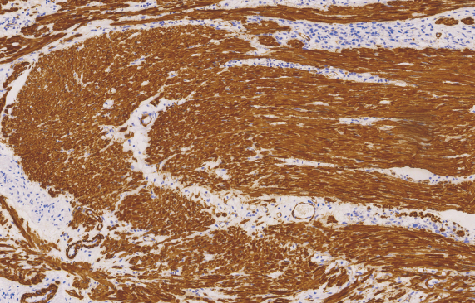

Muscle Specific Actin(MSA)鼠抗人广谱肌动蛋白单克隆抗体

肌动蛋白(Actin)是微丝的蛋白组份,微丝作为普遍存在的细胞骨架成分存在于大多数细胞中。Actin根据生物化学和免疫学性质分头三个主要的亚型: a-Actin存在于肌组织中。B和v-Actin存在于非肌细胞中。小部分v-Actin存在于肌细胞中

- 阳性部位:胞质

- 适用组织:石蜡切片 /冰冻切片

) 这种抗体用于检测肌上皮及平滑肌细胞以及这方面来源的肿瘤,它适合于各种组织切片,抗原修复后可获得更好的结果。 3.肌动蛋白(Actin) 肌原纤维由两种成分组成,细肌丝和粗肌丝。细肌丝则由肌动蛋白,原肌球蛋白和肌原蛋白三种成分组成,其中的肌动蛋白,其分子呈球状,它们互相连接形成长链,每一条细肌丝都由两条肌动蛋白分子所构成。 现临床用于检测肌动蛋白的抗体有如下几种: ①单克隆小鼠抗人肌动蛋白,克隆为HHF35。它是一种广谱标记抗体,既可以用于检测